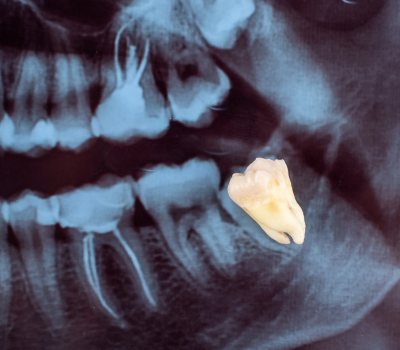

Wisdom teeth, also known as third molars, are the last set of teeth to emerge, typically between the ages of 17 and 25. While some individuals have no issues with their wisdom teeth, many experience complications due to lack of space, improper alignment, or impaction. When these teeth grow at the wrong angle or remain trapped beneath the gums, they can lead to severe pain, swelling, infection, and even damage to surrounding teeth. At Gentle Dental Clinic, we specialize in safe and minimally invasive wisdom tooth extraction, ensuring a smooth, pain-free experience that protects long-term oral health. Whether your wisdom teeth are causing discomfort now or have the potential to create problems in the future, our expert dental team provides personalized care and advanced surgical techniques to ensure a quick recovery and long-lasting results.

Not all wisdom teeth require removal, but when they cause issues, prompt extraction is the best way to prevent ongoing pain and complications. Common signs that indicate the need for removal include persistent jaw pain, swelling in the gums, difficulty opening the mouth fully, frequent infections, or pressure against adjacent teeth. In some cases, wisdom teeth can contribute to crowding, shifting of other teeth, or cyst formation, which can compromise the health of the jawbone. Our dental specialists at Gentle Dental Clinic carefully assess X-rays and oral examinations to determine whether extraction is necessary. By addressing these issues early, we help patients avoid future discomfort and expensive restorative treatments.

At Gentle Dental Clinic, we prioritize patient comfort and advanced surgical precision to make the wisdom tooth extraction process as stress-free as possible. The procedure begins with a detailed consultation and imaging scans to evaluate the position of the wisdom teeth and identify any risks. On the day of the extraction, we use local anesthesia or sedation options to ensure a completely painless experience. If the wisdom tooth is impacted, our skilled surgeons carefully remove small sections of bone or gum tissue to access the tooth without unnecessary trauma. Our advanced techniques help minimize bleeding, reduce swelling, and promote faster healing, allowing patients to recover comfortably. With our expert approach and state-of-the-art tools, we ensure that every extraction is efficient, precise, and safe.